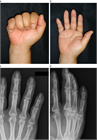

1. 骨折する部位により特徴的な変形を呈する。

1. 関節拘縮を起こさないような内固定と外固定が必要であり、解剖の熟知が重要である。